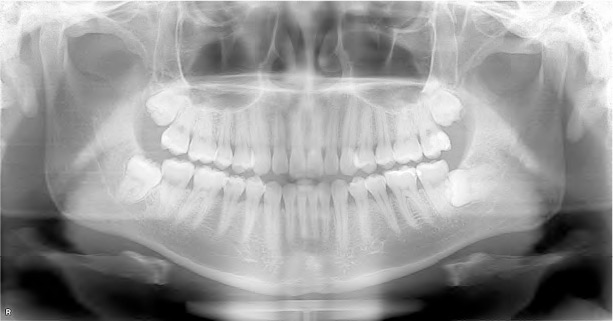

牙科領域的X光檢查主要分為口內和口外X光片。在牙科診療中使用的X光機,產生輻射屬於非常低劑量的電離輻射,遠低於已知肯定會傷害人體的水平。例如口內拍攝的「根尖片」,單次檢查的有效輻射量約為0.004毫西弗(mSv) ,與一天在自然環境中吸收到的有效輻射量(約0.006mSv)差不多。